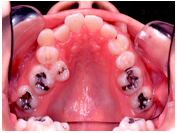

(注) この患者さんの治療の詳細は、院長の治療例の「叢生」(ここをクリック)で詳しく解説しておりますので、治療の方法や期間、治療費、リスク等はそちらを参照してください。